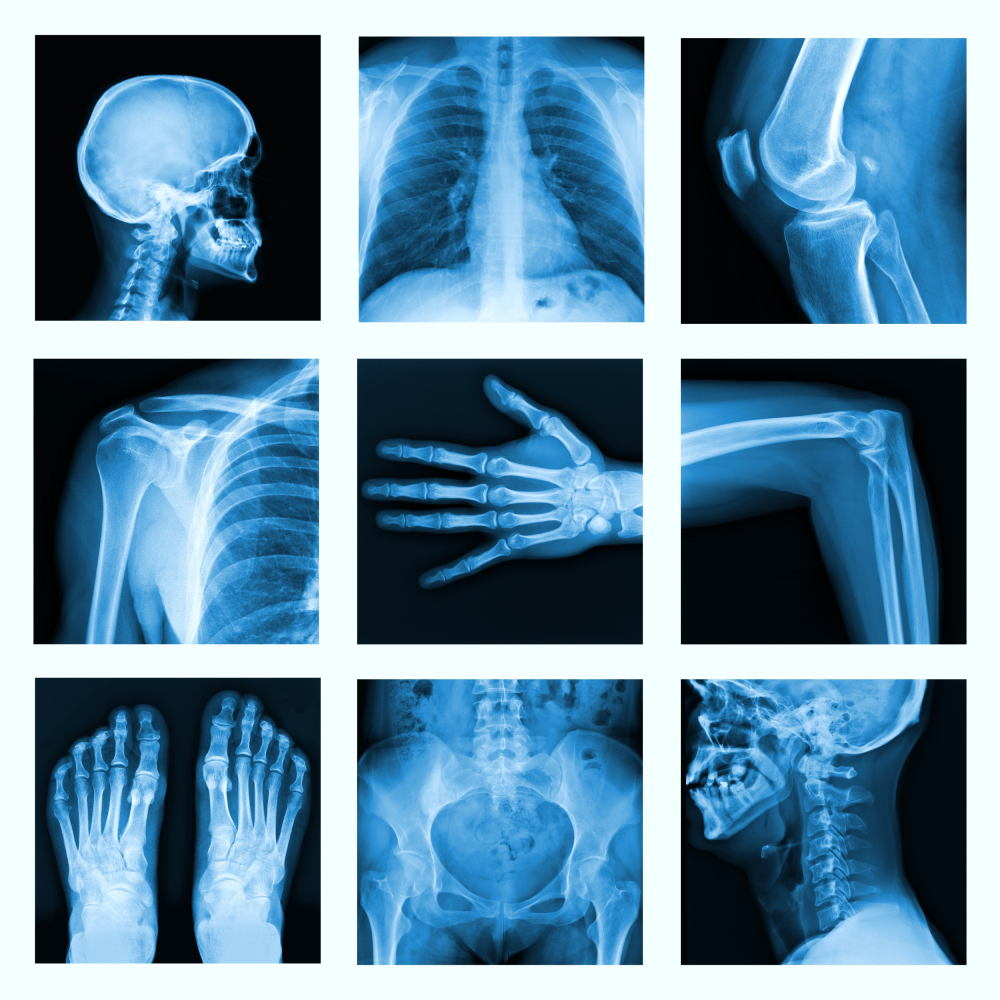

An X-ray is a common imaging test that’s been used for decades. It can help your doctor view the inside of your body without having to make an incision. This can help them diagnose, monitor, and treat many medical conditions.

Different types of X-rays are used for different purposes. For example, your doctor may order a mammogram to examine your breasts. Or they may order an X-ray with a barium enema to get a closer look at your gastrointestinal tract.